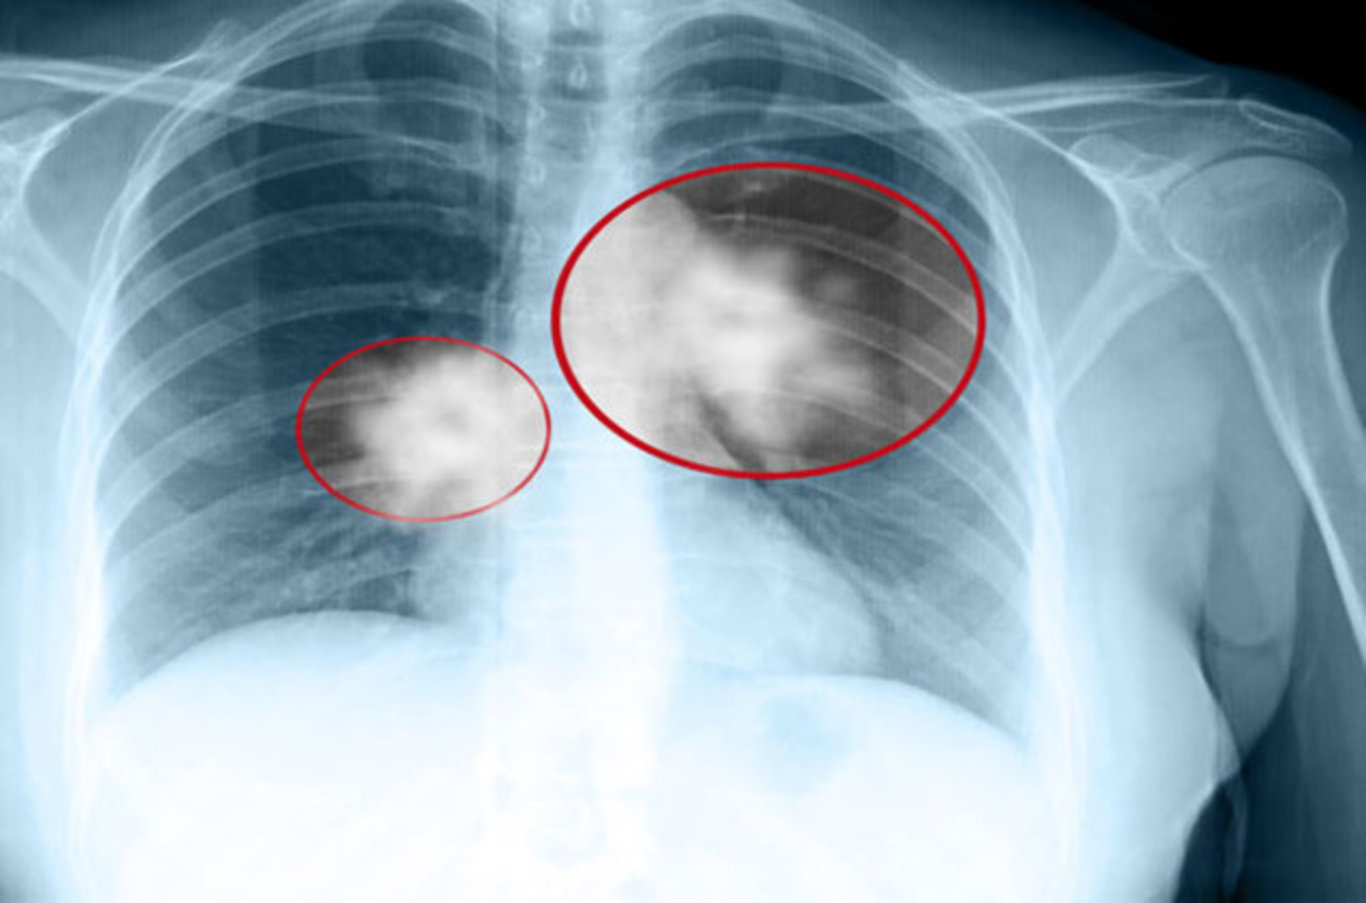

Akciğer kanserinin erken evrede teşhis edilebilmesi için belirtilerde zaman kaybetmeden doktora başvurulması ve yakınması olmasa dahi sigara içen 40 yaş üstü kişilerin yıllık akciğer tomografilerini yaptırmaları çok önemli. Uzmanlar bu konuda sık sık uyarılarda bulunurken, aynı zamanda akciğer kanserinin 8 belirtisi hakkında da bilgilendirme yapıyor. İşte detaylar…